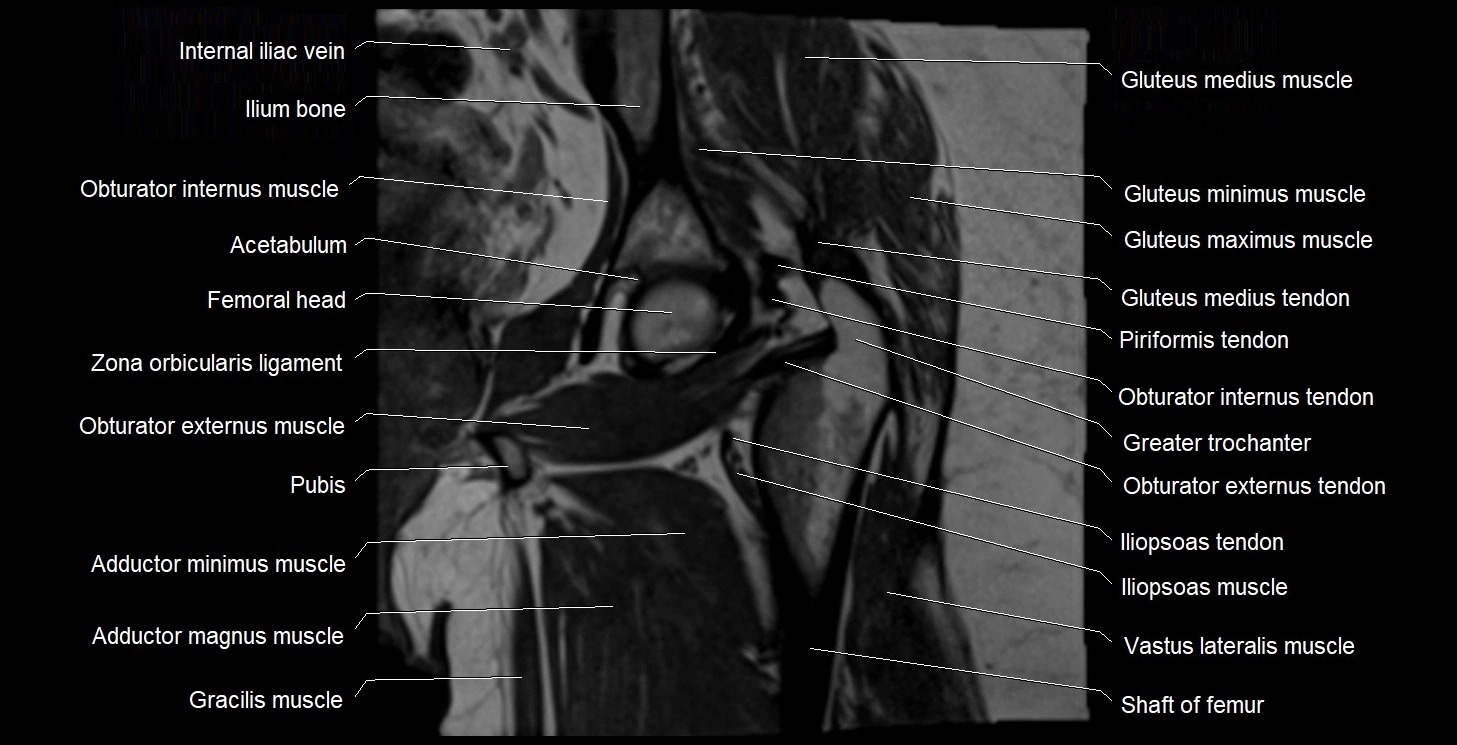

- Acetabulum

- Greater trochanter

- Head of femur

- Iliopsoas muscle

- Iliopsoas tendon

- Ilium bone

- Obturator externus muscle

- Obturator internus muscle

- Obturator internus tendon

- Vastus lateralis muscle

- Zona orbicularis ligament